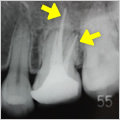

抜髄症例

主訴:3日前から何もしなくても前歯が痛む

- 虫歯が大きく神経まで達している為、虫歯を除去し抜髄

- ファイルを使って根の長さを測定・根管形成(根管-神経が入っていた管-を根管充填しやすい形に整えること)

- 根管充填剤が根尖(根の先端)まできっちりと充填